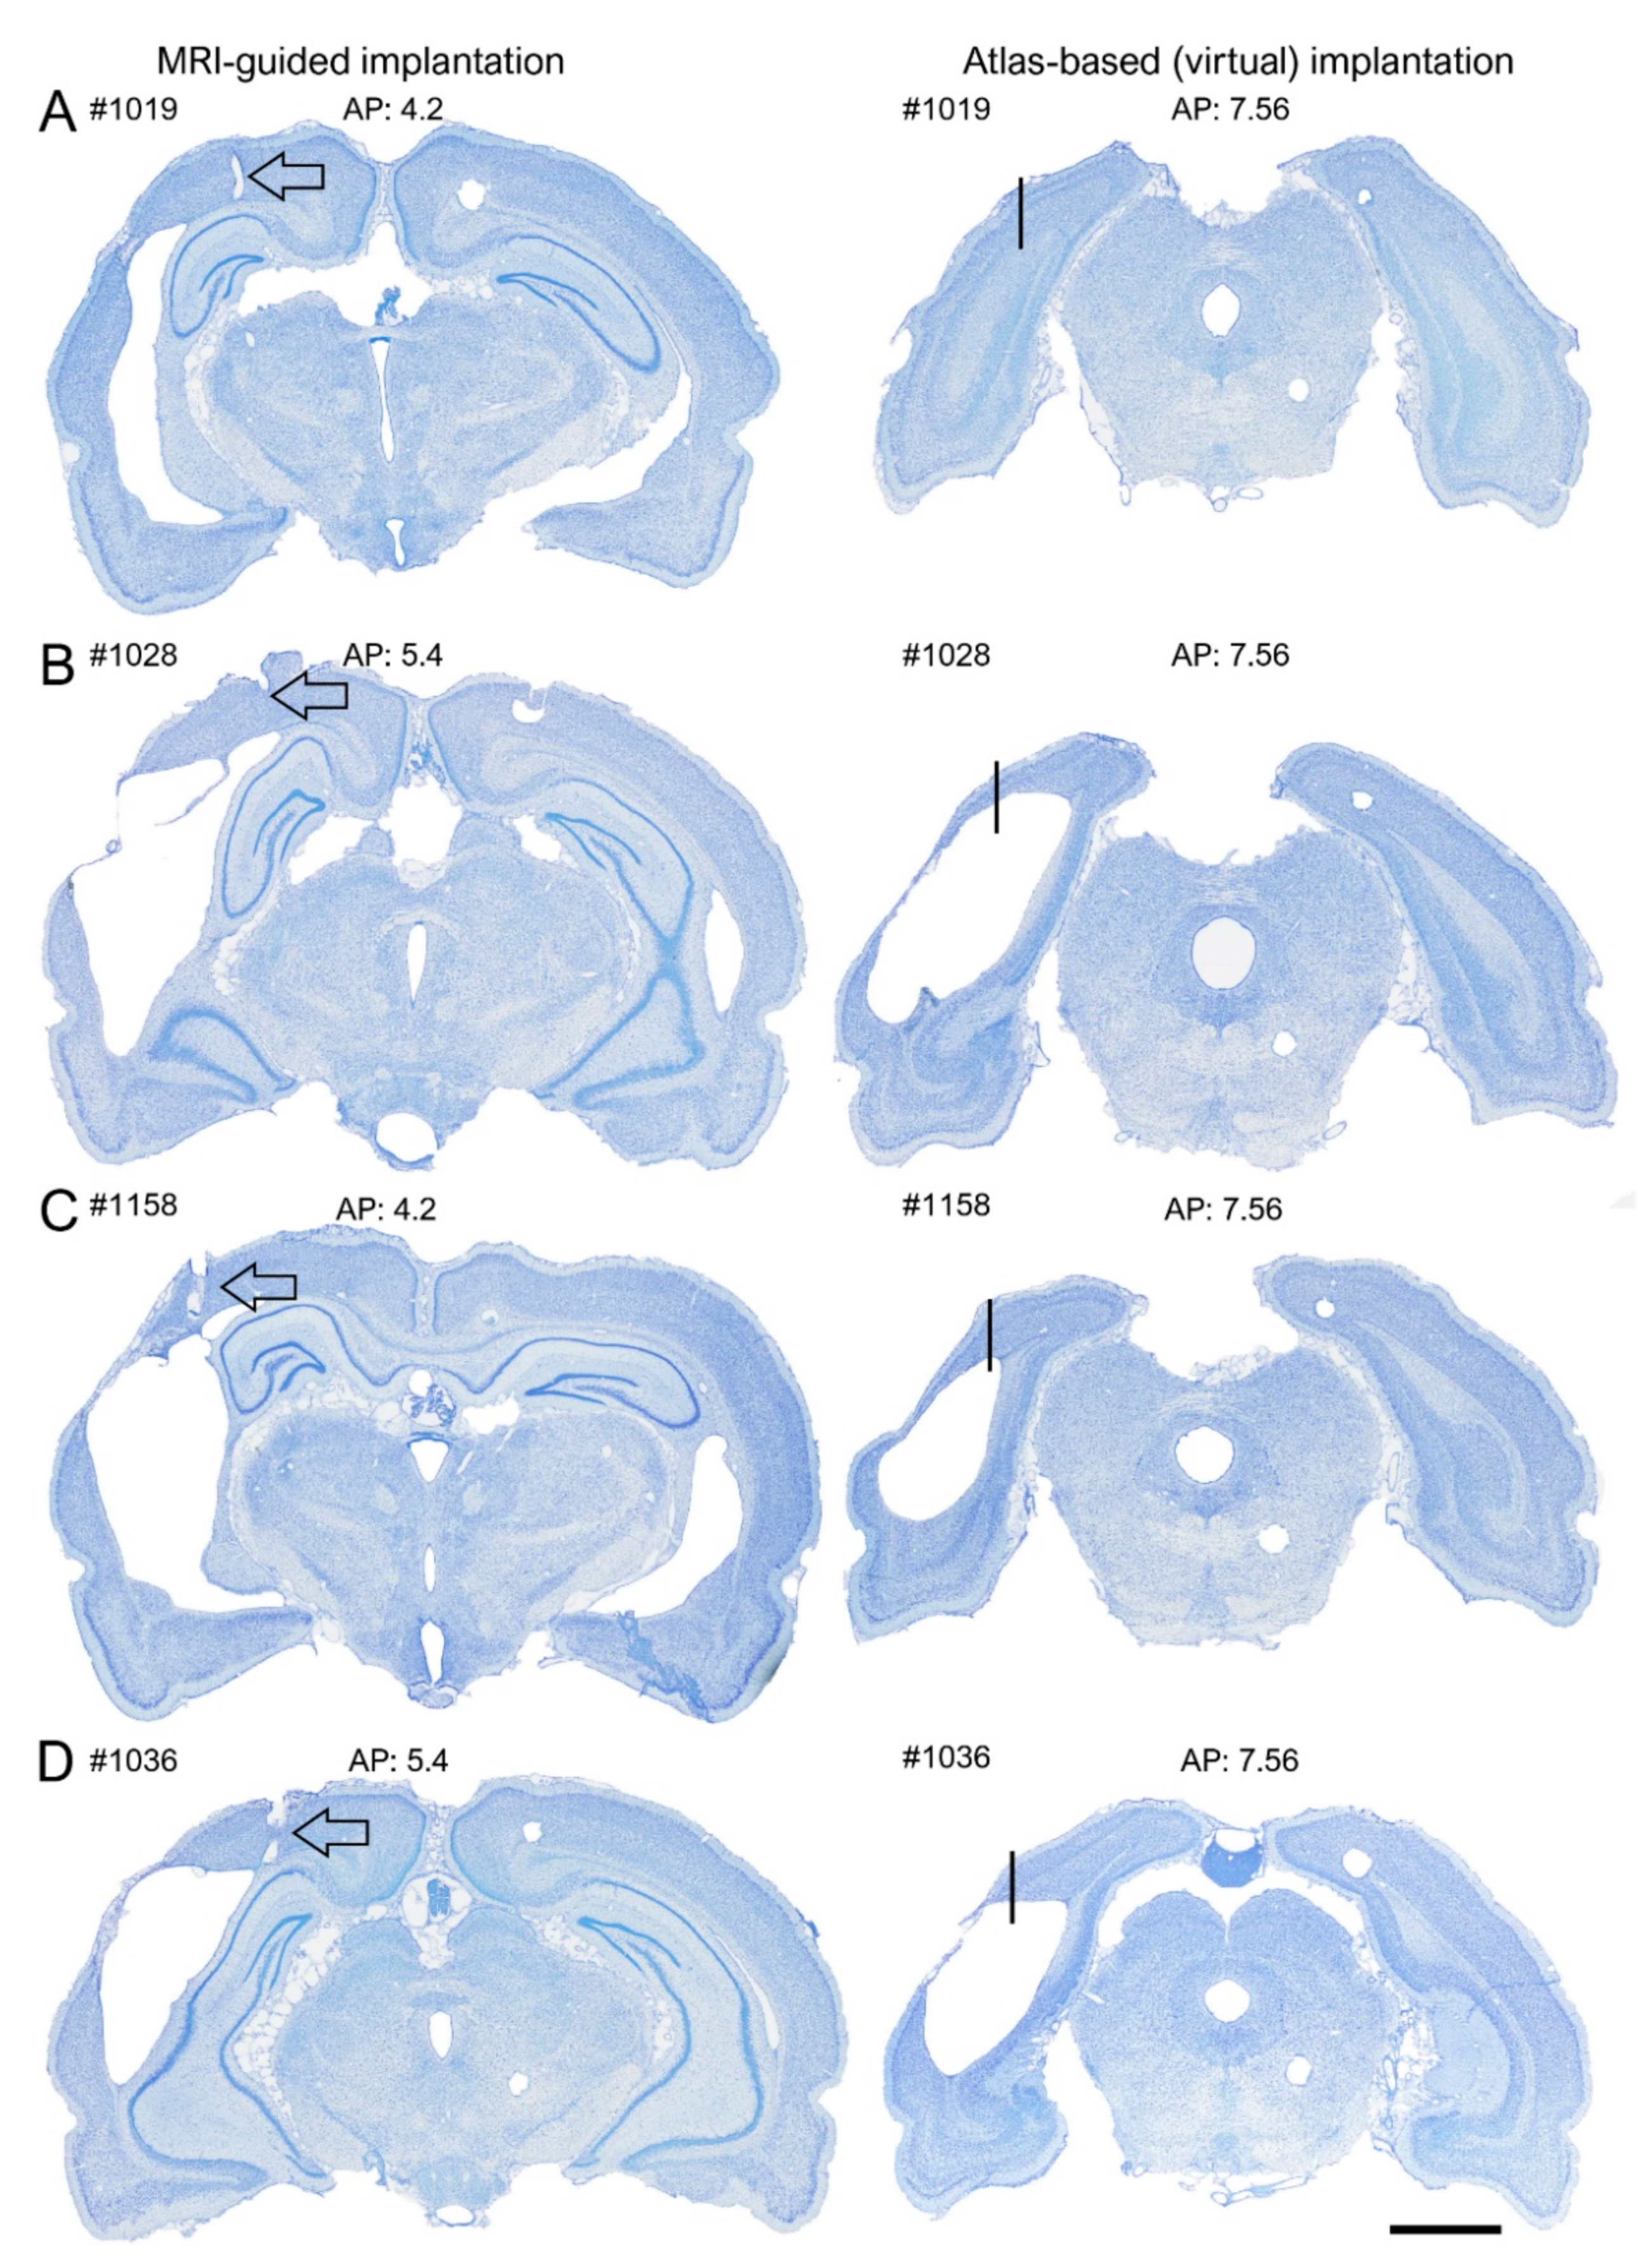

A hypothetical “virtual” electrode was placed at the atlas-defined coordinate of the posterior intracortical electrode (Figure 10). We then reconstructed the destination of the electrode tip in the available histological sections by assessing (a) whether it was located in the cortex or lesion cavity and (b) the distance of the tip from the lesion edge. We found that by using the atlas-based coordinate (AP −7.56), 58% (18/31) of the electrodes had been in the lesion cavity compared with 0% for the MRI-guided implantations (Figure 5C and Figure 10 and Table 2). The remaining 42% (13/31) of the “virtual” electrodes were located medial to the lesion cavity, except in one case (rat 1103), in which the tip location was caudal to the lesion. The average distance of the electrode tip to the lesion edge was 0.64 ± 0.1 mm (range: 0–1.3 mm) (see also Supplementary Table S2 for further details).

Figure 10.

Location of electrode tip at 5 months postinjury without prior MRI analysis. Photomicrographs of thionine-stained coronal brain sections of 4 animals; (A) #1019, (B) #1139, (C) #1158 and (D) #1036 in the MRI cohort with electrode implantations at 5 months after TBI. Left panels: MRI-guided placement of the posterior cortical electrode. Note that all electrodes are within the perilesional cortex. Right panels: The location of the electrode tip (arrow), if the electrode was implanted according to the targeted atlas-based coordinates (−7.56 mm from bregma, 4 mm from midline, 1.8 mm from the surface of the brain). Note that in all rats except 1019, the electrode tip ended in the lesion cavity. Table 2 summarizes the locations for all cases. Scale bar = 2 mm.

Table 2.

Location of the “virtual electrode”. Summary of the locations of the posterior intracortical electrodes in the MRI cohort, if implanted according to the atlas-based coordinates. Note that 58% (18/31) of the lower electrode tips were in the cortex while 42% (13/31) of the lower tips were in the lesion cavity. After MRI-guidance, 71% (22/31) of the lower tips were recording in the cortex. In 5 additional cases, the upper tip (0.5 dorsal to the lower tip) was expected to record in the cortex, resulting in a total of 87% (27/31) of the electrodes recording in the cortex. Only 1 electrode was not recording in the brain.